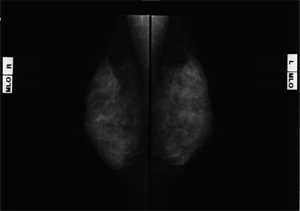

マンモグラフィ(乳房エックス線写真)検診施設画像認定(マンモグラフィ検診精度管理中央委員会)

乳房は柔らかい組織でできているため、専用のX線撮影装置を使用します。乳房を板で挟むため痛みが生じますが、乳房を薄くするほど「被ばく」が減り、きれいな写真を撮影することで、病変の早期発見につながります。検査を受けられる方のご理解・ご協力がとても大切になります。